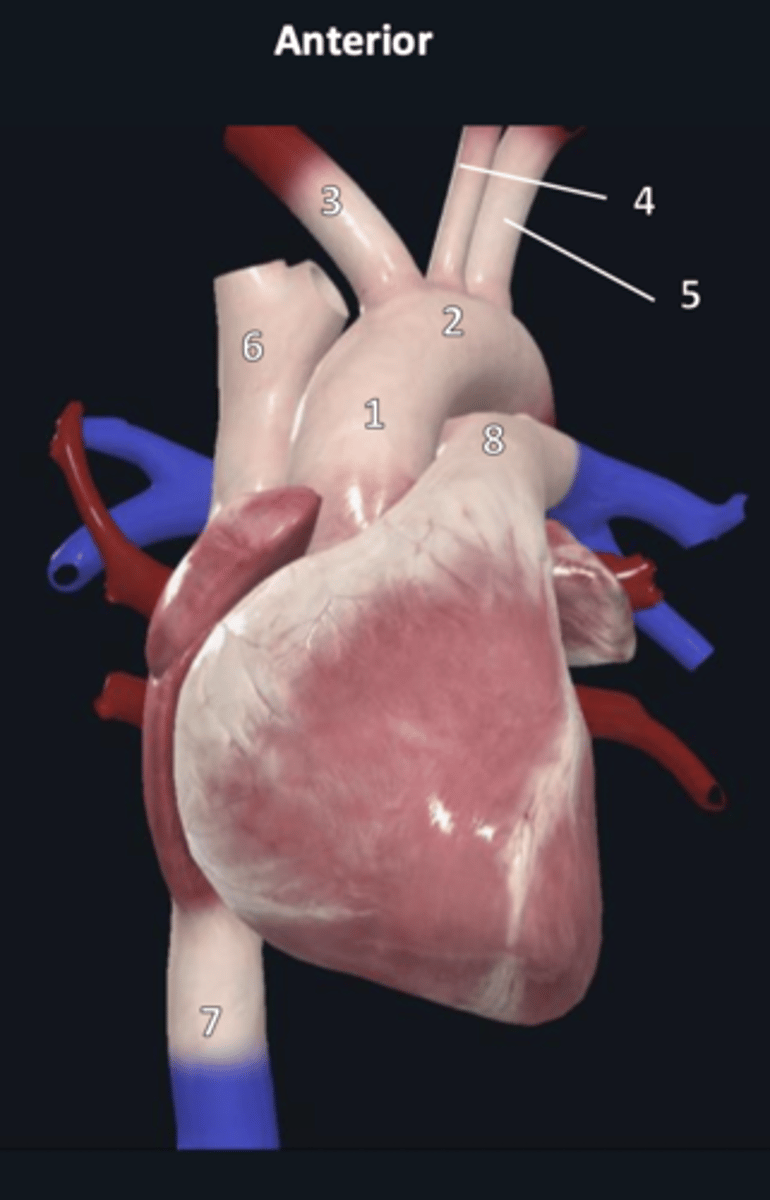

ascending aorta

1

aortic arch

2

brachiocephalic trunk

3

left common carotid artery

4

left subclavian artery

5

superior vena cava

6

inferior vena cava

7

pulmonary trunk

8

pulmonary arteries

9

pulmonary veins

10

ligamentum arteriosum

11